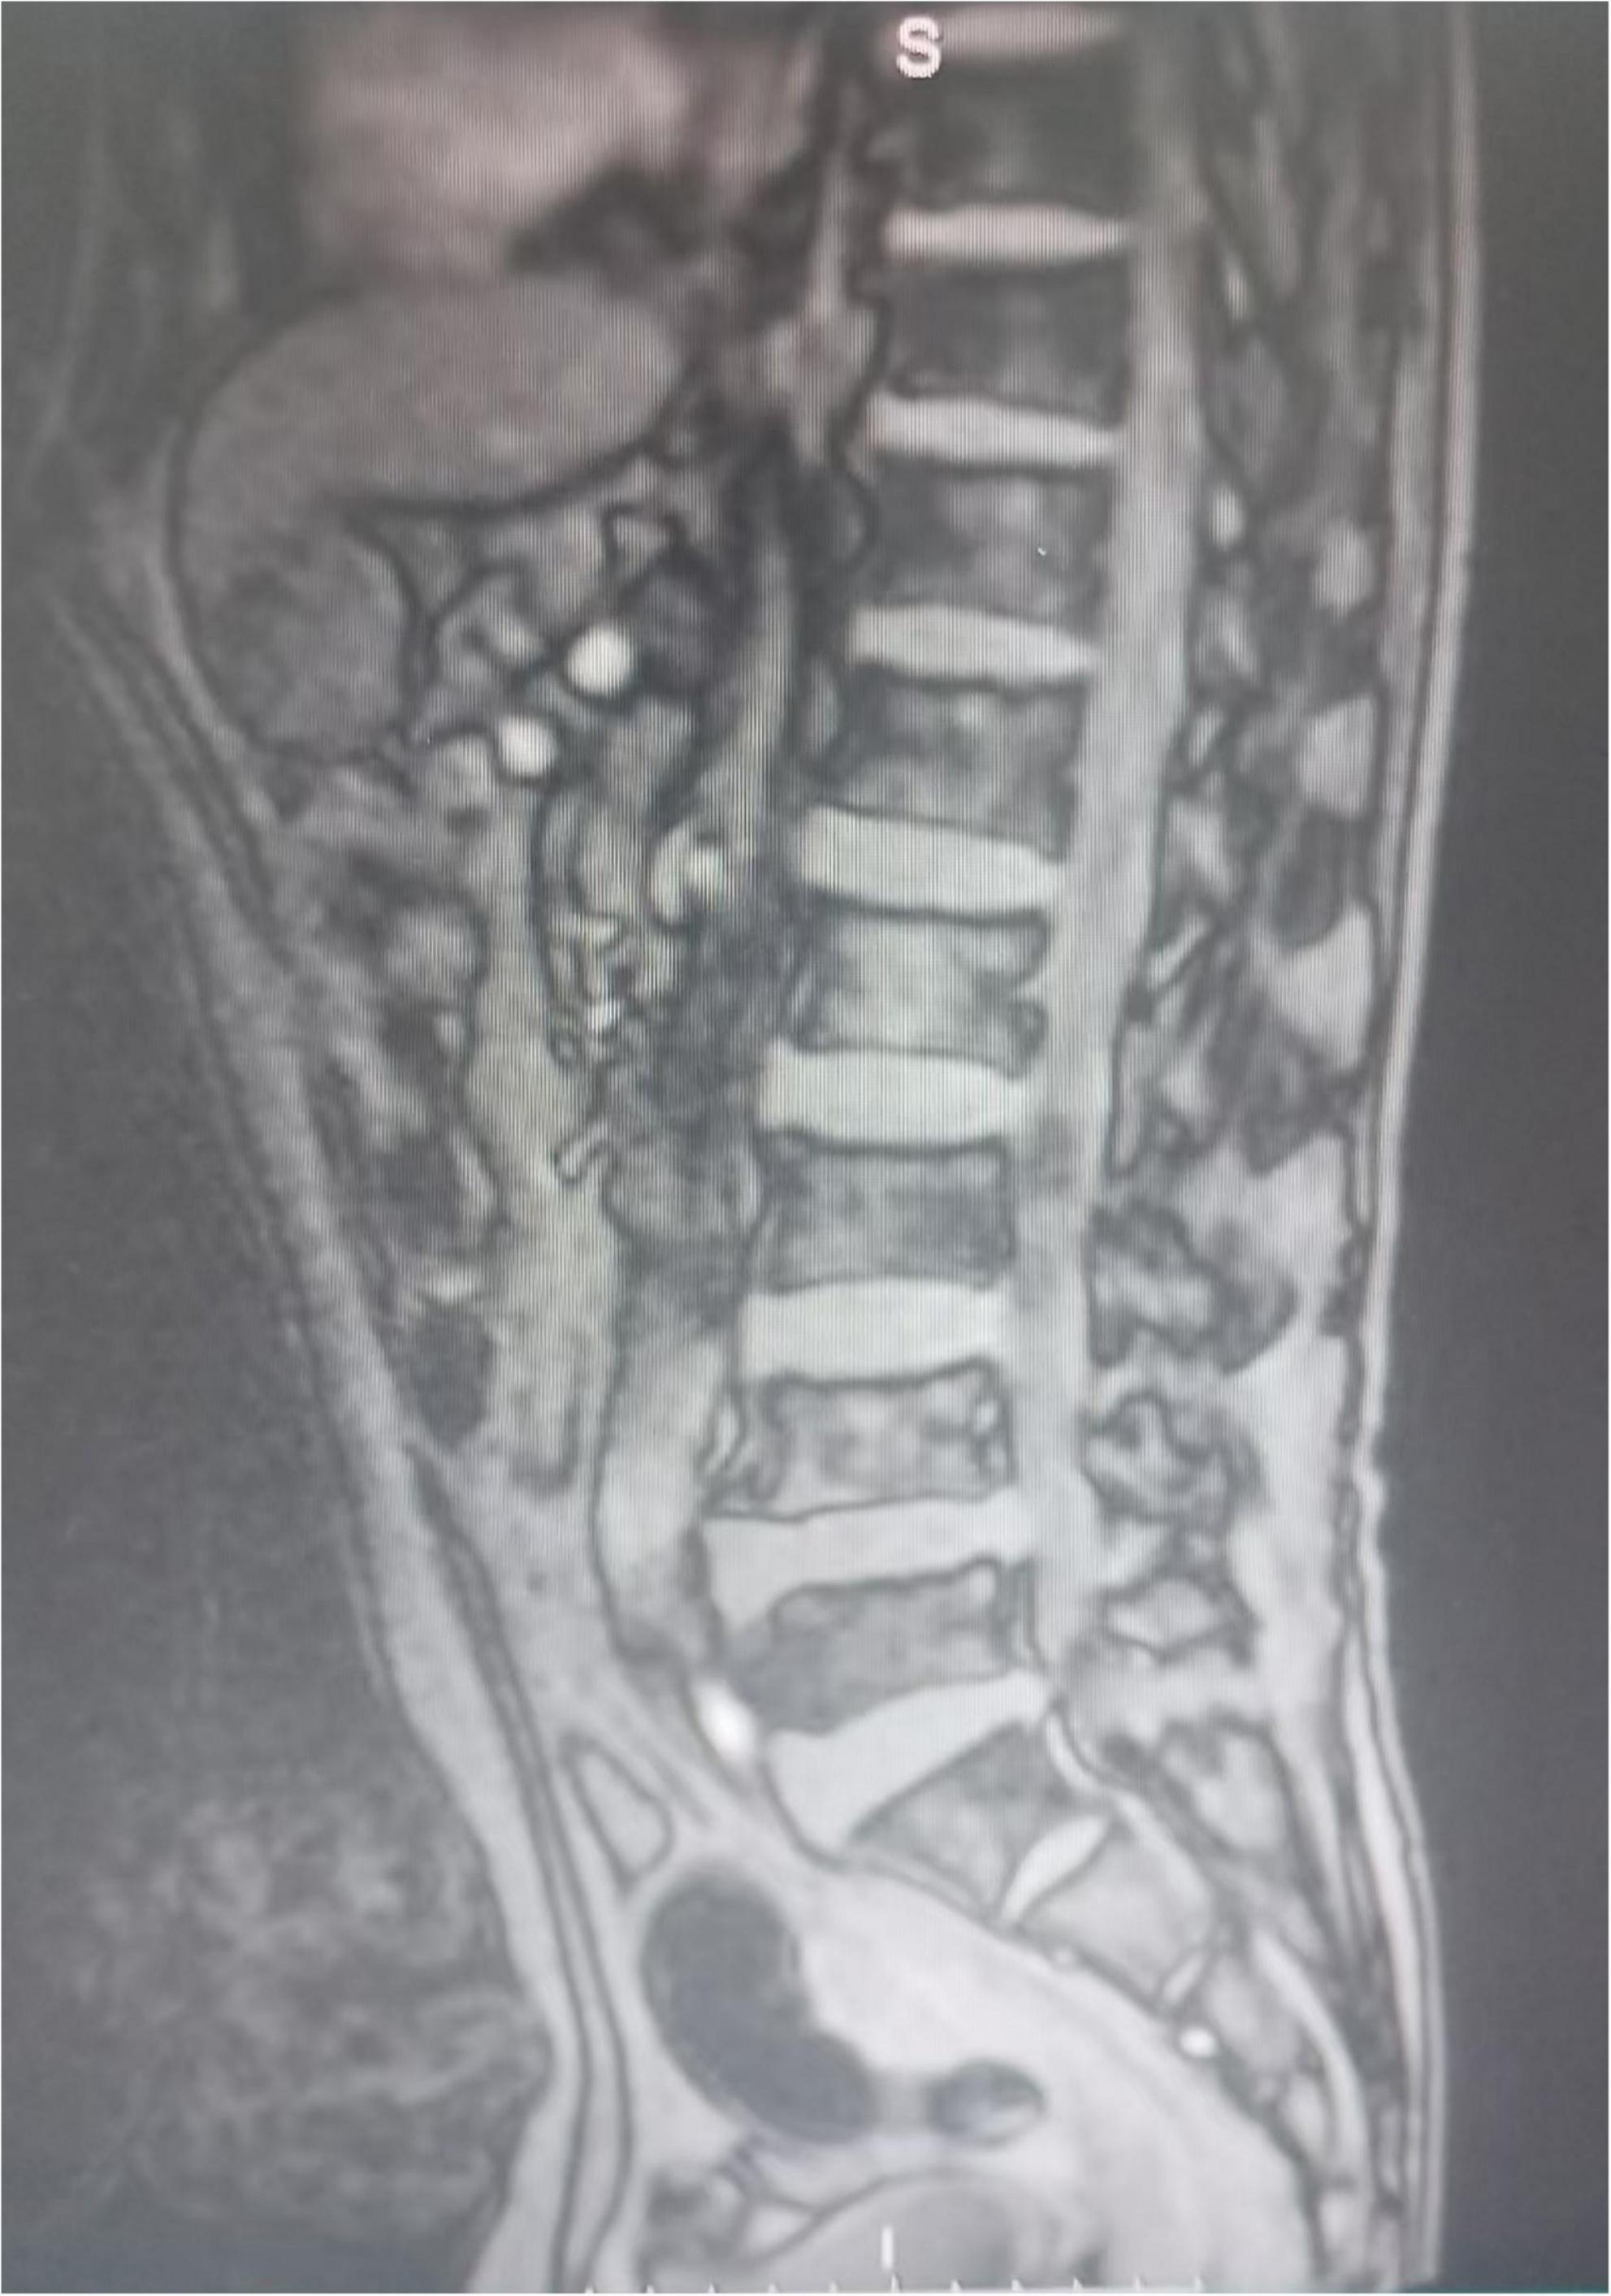

FIGURE 3

The patient’s spinal MRI showed no abnormalities.